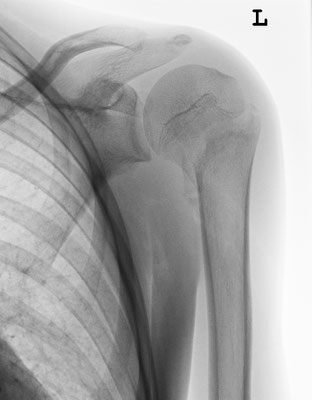

13-jähriger Junge mit Oberarmkopfbruch (Abb.1). Nicht operative Behandlung. Abb.2 zeigt das Röntgenbild nach 1 Jahr. Abb.3 zeigt die Funktion nur 2 Monaten nach dem Unfall!